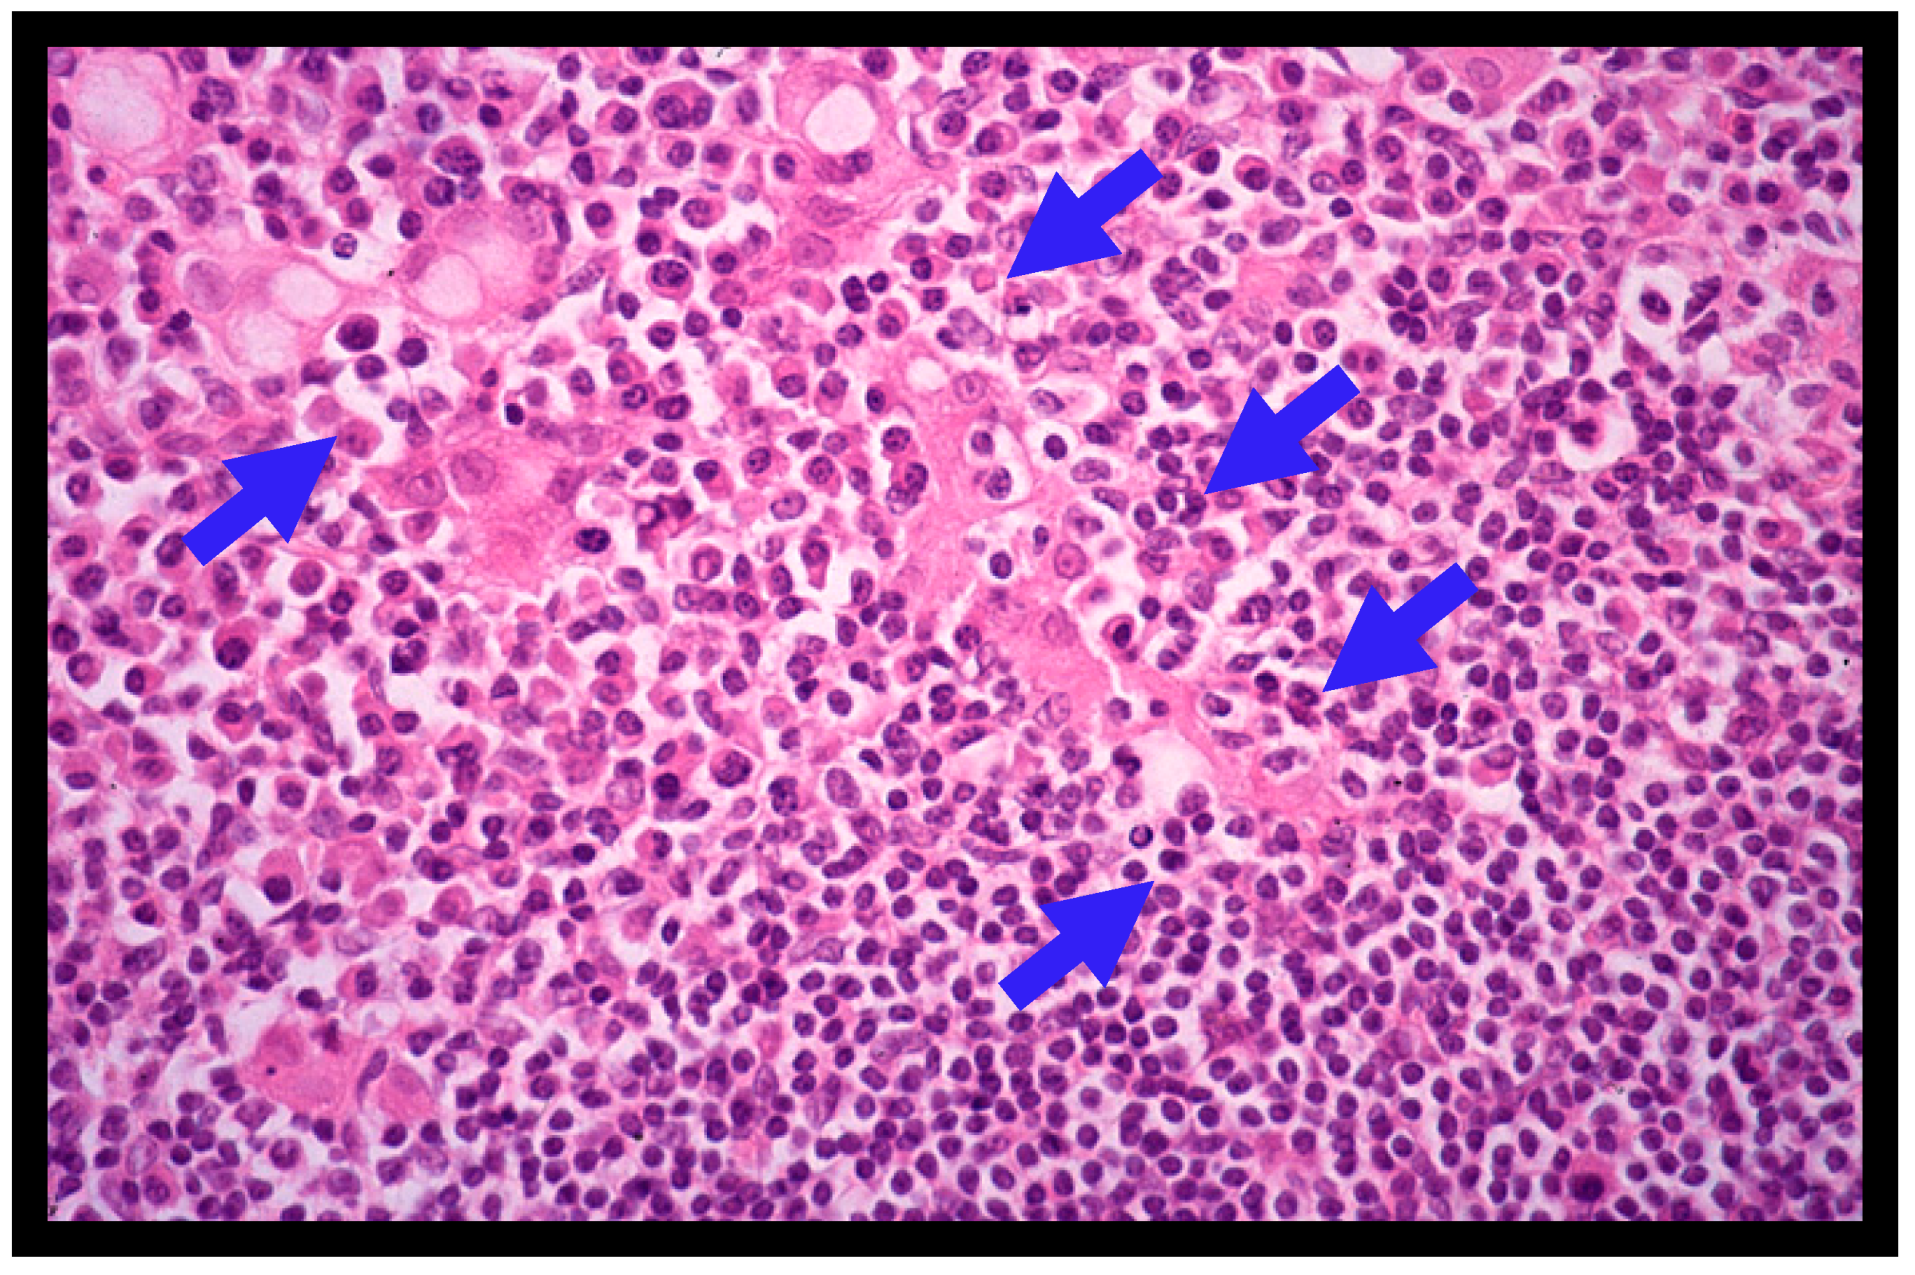

4.2. Histopathology of Gastric MALT Lymphomas